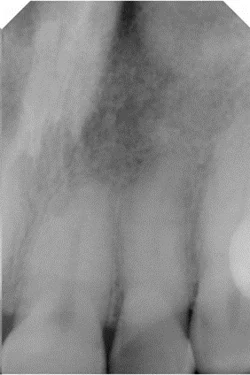

Natuurlijk was mijn eerste gedachte dat dit een niet-vitaal gebitselement was, bijvoorbeeld door een eerdere endodontische behandeling. Ik dacht we dit probleem gemakkelijk konden oplossen met een bleekbehandeling voor niet-vitale gebitselementen. Maar uit de röntgenopname (afbeelding 2) en een vitaliteitstest bleek het element nog in leven te zijn. Het reageerde heel goed op de thermische vitaliteitstest. Bovendien waren er geen tekenen van een toegangscaviteit op het palatinale vlak. Misschien was de verkleuring veroorzaakt door trauma? Ik vroeg de patiënte waarom haar tand donkergekleurd was.

Afbeelding 2: Röntgenopname: bewijs van vitaliteit van het gebitselement

Haar verhaal maakte duidelijk dat het cruciaal was om nog eens heel gedetailleerd naar deze casus te kijken. Wat was er precies met het gebitselement gebeurd na de stoot die tot het trauma had geleid? Het element was niet alleen oppervlakkig verkleurd. Er bleek binnenin sprake te zijn van dystrofische calcificatie als reactie op het trauma, met als gevolg de ongewenste verkleuring. Dit is een interne verandering in het anorganische gedeelte van het gebitselement. Het kan worden waargenomen door een nauwkeurige analyse met behulp van röntgen.